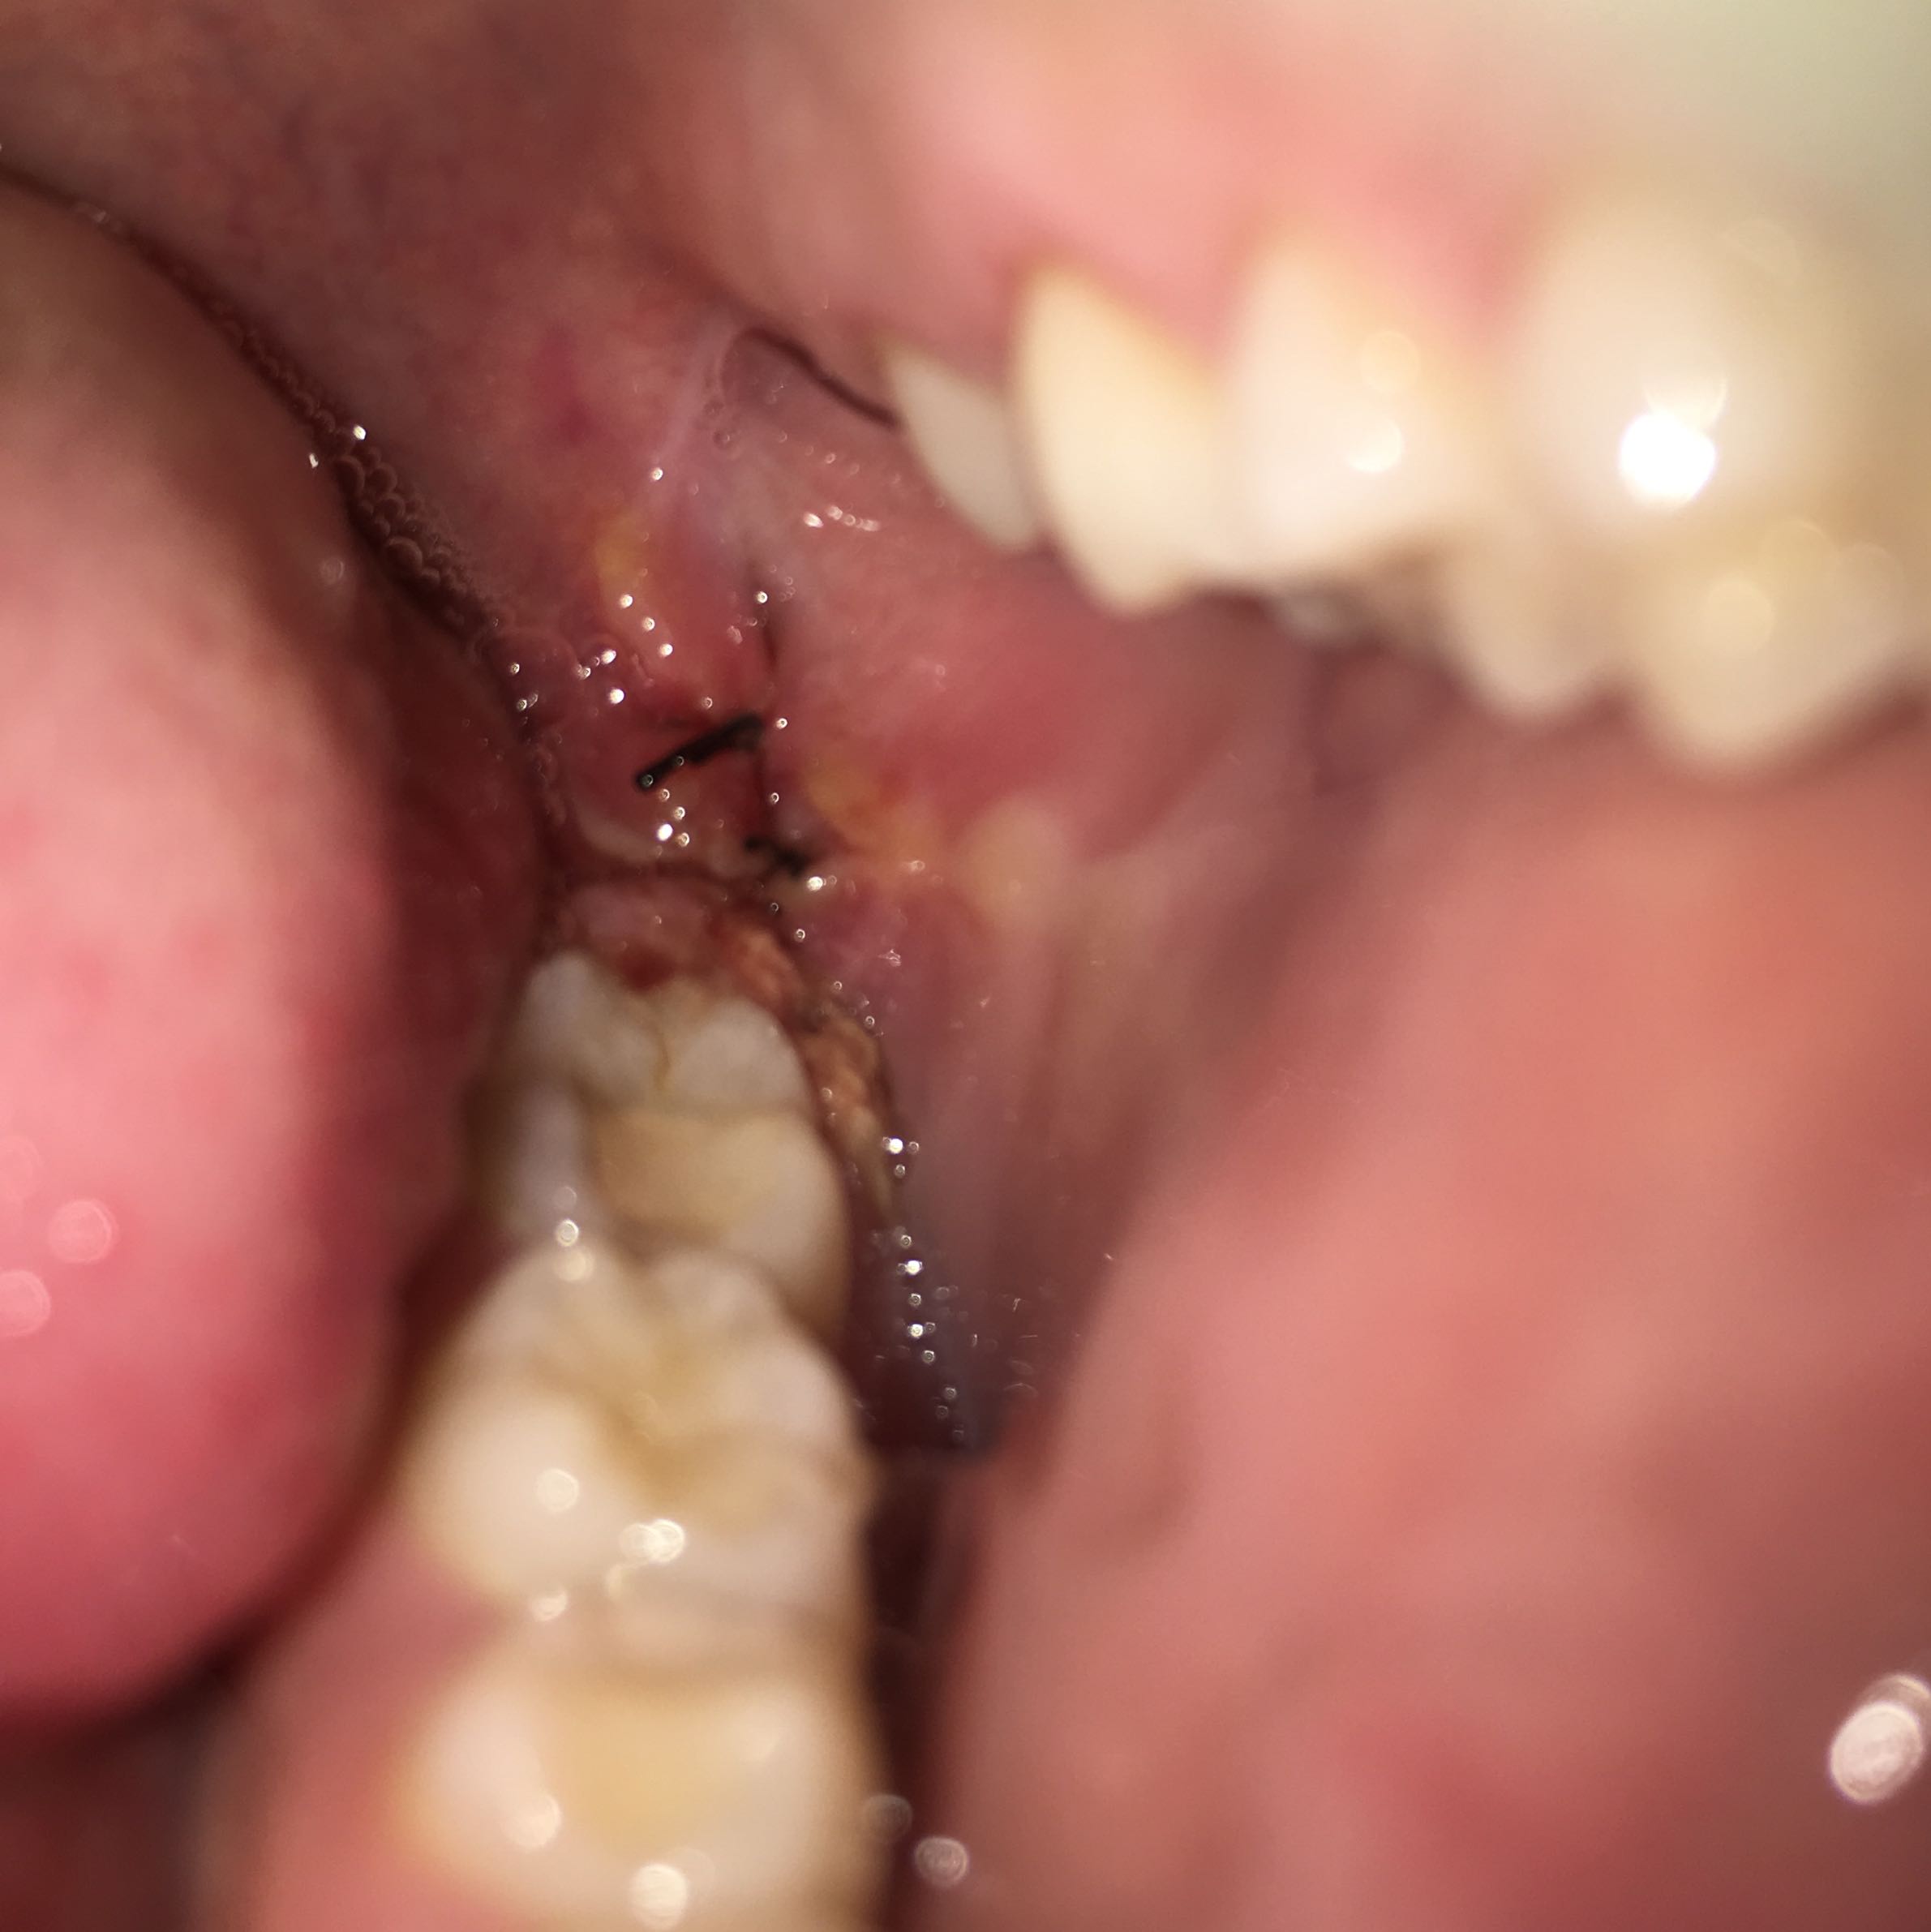

Entzündung nach einer Weisheitszahn OP

Die Fäden werden normalerweise nach 7 bis 10 Tagen entfernt. Du kannst nach einer Weisheitszahn-OP in der Regel nach 24 Stunden wieder Schokolade essen.2022 06:00 Uhr. Ob nach einem Schnitt mit dem Küchenmesser . 30 Minuten auf ein Tuch oder auf eine Kompresse zu beißen.Lebensmittel, die die Wundheilung im Mund fördern. Wenn du Schmerzen oder Schwellungen nach der Operation hast, solltest du deinen Zahnarzt kontaktieren und dich erkundigen, was du tun kannst, um es zu lindern.Wir empfehlen dir, die Kompressen mindestens die ersten zwei bis drei Tage nach der Verletzung anzuwenden.Weisheitszähne: Schmerzen, Symptome und Ablauf der OP. Dabei gibt es in der Regel keine .Nach einer Weisheitszahn-OP sollte man mindestens 48 Stunden warten, bevor man wieder Kaffee trinkt, um die Heilung nicht zu beeinträchtigen.